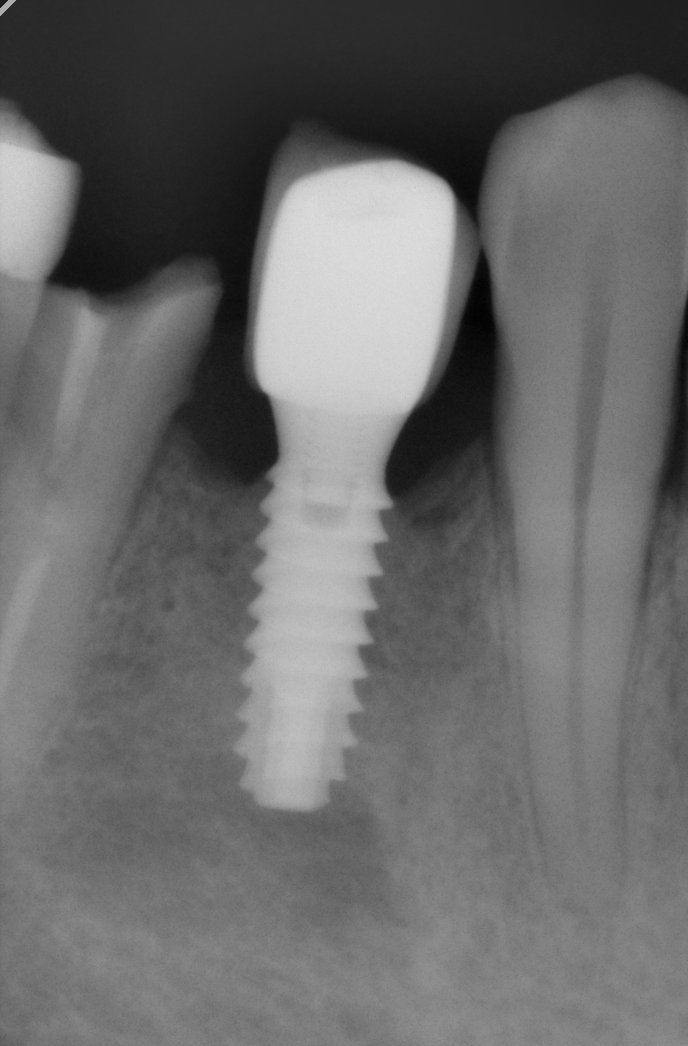

Buenas tardes, Necesitamos averiguar la marca de Implante de la pieza 44. Sabemos que es una corona atornillada. Muchas gracias.